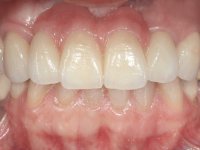

The patient did not like her smile, said that she had "very artificial looking teeth".

In view of the clinical situation, oral rehabilitation was proposed to improve the aesthetic appearance, but also to solve the lack of posterior teeth, seeking a functional and aesthetic rehabilitation. The plan included replacing the metal-ceramic bridge by a bridge with Zr infrastructure coated with coronary and gingival ceramics. The edentulous area of the first quadrant would be rehabilitated with 2 implants and a bridge of two elements. It was intended with this treatment plan, to recover the vertical dimension of the occlusion and to reshape the dental anatomy, thus creating a more natural aesthetic appearance.

Alginate impressions were made at both arches arcades, accompanied by intermaxillary registration relations and collecting information with facial bow facial bow. In the laboratory, a provisional bridge with 13 elements in autopolymerizable acrylic was built, in which a metallic reinforcement was included. Teeth 1.7 / 1.4 / 1.3 / 2.2 / 2.3 / 2.4 and 2.6 were used as pillars. The metal-ceramic bridge was removed after performing longitudinal cuts with diamond burs. The dental abutments were reprepared and the temporary bridge was relined in the mouth with self-curing acrylic. After confection of the provisional bridge, a gingival epithesis was made using composite resin with gingival tonality in order to function as a mock-up, which allowed the patient to preview the possibility of using gingiva shade ceramics in the final work. This option was approved by the patient. Subsequently, the placement of two implants in the first quadrant was planned and executed. The provisional monoblock was removed for placement of the implants, and after surgery was again cemented provisionally. After the osseointegration period, the impressions were made to the maxilla. In the anterior zone, impregnated gingival retraction cords were used, and in the posterior areas, kaolin paste was used. Implant printing utilized the open tray technique. The printing material used was soft and regular putty addition silicone, both fast-setting. In the laboratory, the model of provisional restorations and the gingiva epithesis mock-up served as orientation for waxing the infrastructure. The plaster work model and the waxing of the infrastructure were placed in a laboratory scanner and yielded a digital work model, in which the scanning of the waxed infrastructure was superimposed. This overlay facilitated the CAD design of the Zr infrastructure. Subsequently, the CAD drawing for a CAM milling process provided the Zr pieces. The infrastructure was pigmented with a pinkish coloration, which favors the subsequent placement of gum shade ceramic. During the modeling of the infrastructure, the need to increase the occlusal wear on tooth 1.4 was detected. This was done in the real working model cast and an acrylic wear control guide was created, which accompanied the proof of the infrastructures. Corrective wear and Zr parts test were performed in mouth. During the test, the color choice of the gum shade ceramic was reassessed. The treatment was finished in the laboratory, and after approval by the patient, was definitively placed in the mouth.